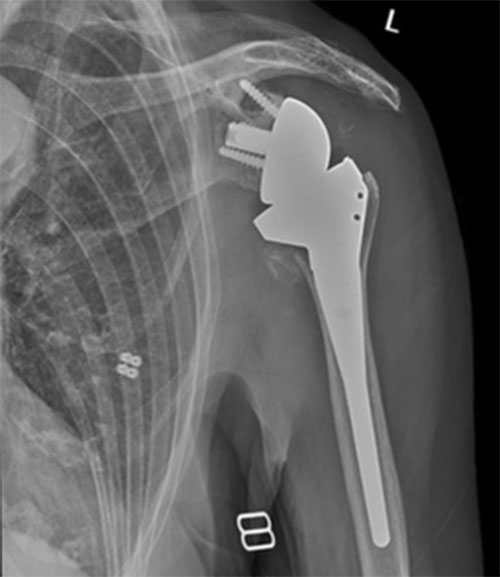

Shoulder after reverse replacement surgery

Shoulder before reverse replacement surgery

Move the slider to compare cuff tear arthropathy and superior migration of humeral head with left reverse total shoulder replacement